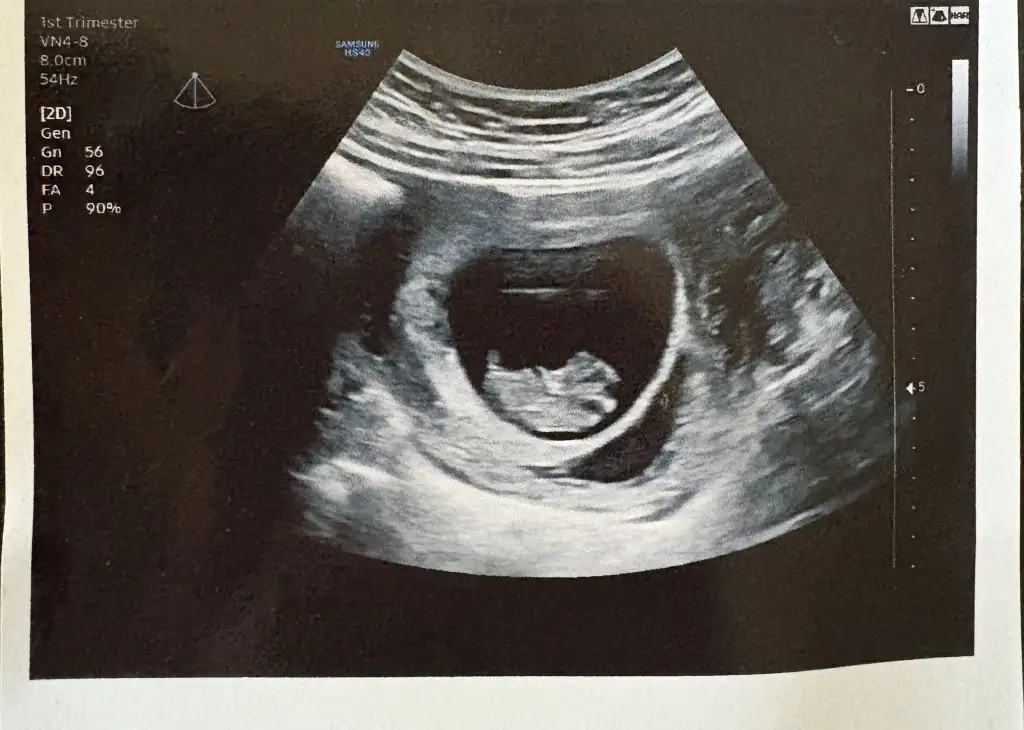

Selamünaleyküm canm öncelikle hiç korkma bisi olmuyor o bende de vardı bisi olmuyor yani 12. Haftada falan kayboldu kese büyüdükçe kayboluyor bana hatta progestan vermişti doktorum o bana yan etki yaptı bıraktım ama yine de kayboldu 5 gün kullanabildim sadece ama merak etme gidiyor sadece dikkat et9 haftalık hamileyim 5.haftanın sonunda bebeği ve kalp atışını görmüştük o gün kanama alanı tespit edildi doktor progestan fitil başlattı bugün kontrolüm vardı kanama alanı hala duruyor bebek sağlıklı görünüyor çok şükür doktor büyümemişte küçülmemişte ama yok olmadığı sürece her zaman riskli dedi benim dışarıdan bir kanamam lekelenmem olmadı şükür ki ama sürekli risk denmesi çok tedirgin ediyor bu süreci yaşayanlar varsa bilgi almak isterim 12. 16.haftaya kadar kaybolabilir o zamana kadar risk var diyeceğim dedi doktor ama benim düşüncem bir şey olmaz diyor ultrason fotoğrafını da ekliyorum

Benim 4 gebeliğimde de vardı kan sulandırıcı iğne ve ilaç kullanıyorsanız birinin kesilmesi gerek9 haftalık hamileyim 5.haftanın sonunda bebeği ve kalp atışını görmüştük o gün kanama alanı tespit edildi doktor progestan fitil başlattı bugün kontrolüm vardı kanama alanı hala duruyor bebek sağlıklı görünüyor çok şükür doktor büyümemişte küçülmemişte ama yok olmadığı sürece her zaman riskli dedi benim dışarıdan bir kanamam lekelenmem olmadı şükür ki ama sürekli risk denmesi çok tedirgin ediyor bu süreci yaşayanlar varsa bilgi almak isterim 12. 16.haftaya kadar kaybolabilir o zamana kadar risk var diyeceğim dedi doktor ama benim düşüncem bir şey olmaz diyor ultrason fotoğrafını da ekliyorum

Ne durumdasınız? Benim 11. Hafta yoğun kanamam olmuştu şimdi 17. Haftada lekelenmem devam ediyor evde yatıyorum.9 haftalık hamileyim 5.haftanın sonunda bebeği ve kalp atışını görmüştük o gün kanama alanı tespit edildi doktor progestan fitil başlattı bugün kontrolüm vardı kanama alanı hala duruyor bebek sağlıklı görünüyor çok şükür doktor büyümemişte küçülmemişte ama yok olmadığı sürece her zaman riskli dedi benim dışarıdan bir kanamam lekelenmem olmadı şükür ki ama sürekli risk denmesi çok tedirgin ediyor bu süreci yaşayanlar varsa bilgi almak isterim 12. 16.haftaya kadar kaybolabilir o zamana kadar risk var diyeceğim dedi doktor ama benim düşüncem bir şey olmaz diyor ultrason fotoğrafını da ekliyorum

Benim de kanama alanı var şuan bebek 5 haftalık. Kese göründü ama yolk sac görünmedi9 haftalık hamileyim 5.haftanın sonunda bebeği ve kalp atışını görmüştük o gün kanama alanı tespit edildi doktor progestan fitil başlattı bugün kontrolüm vardı kanama alanı hala duruyor bebek sağlıklı görünüyor çok şükür doktor büyümemişte küçülmemişte ama yok olmadığı sürece her zaman riskli dedi benim dışarıdan bir kanamam lekelenmem olmadı şükür ki ama sürekli risk denmesi çok tedirgin ediyor bu süreci yaşayanlar varsa bilgi almak isterim 12. 16.haftaya kadar kaybolabilir o zamana kadar risk var diyeceğim dedi doktor ama benim düşüncem bir şey olmaz diyor ultrason fotoğrafını da ekliyorum

Benim 6. Haftada göründü endişelenmeyin bazen 7 haftadada görülebiliyormuş allah hakkınızda hayırlısını naaip etsin saglıkl inşallah . Kanama alanım benimde var bi aydır gecmedi hâlâ bende iğne ve fitil devam bebeklerimiz iyi olsun yeter şükürler olsunBenim de kanama alanı var şuan bebek 5 haftalık. Kese göründü ama yolk sac görünmediproges fitil kullanıyorum ben de. Kanamam yok ama içerde kanama alanı var ve geçmiyor 2 haftadır. Yolk sac kaçıncı haftada görünür şuan çok korkuyorum durumumun ne olacağı belli değil